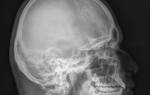

Человеческая речь относится к высшим корковым функциям, для произнесения самого простого предложения требуется интегративная деятельность многих отделов головного мозга и ого аппарата.

Это главнейшее условие коммуникации, без которого невозможно общение с себе подобными. Особенности речи напрямую зависят от образования и кругозора. Нарушение речи у взрослого человека всегда свидетельствует о серьезном заболевании.